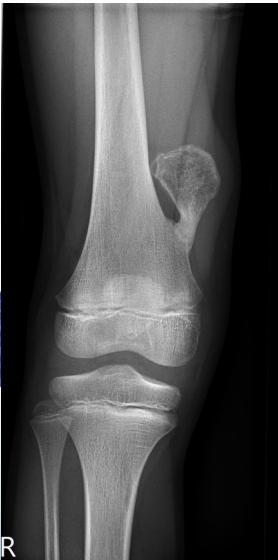

Giant-Cell Tumor

- Unknown origin:

- Giant cells abundant

- Behavior:

- One third benign

- One third locally aggressive

- One third (less) with distant metastasis

- Young adults

- Common sites:

- Around knee

- Proximal humerus

- Distal radius

Radiological Features

- Eccentric lesion:

- Radiolucent

- Soap bubble

- Abuts (adjacent) against the joint

- Thin cortex

- Margins may be clear / unclear:

- Depends on aggressiveness

- Treatment:

- Curettage & bone grafting

- More wide excision in recurrent and aggressive lesions

Source: Bone Tumors A Practical Guide to Imaging